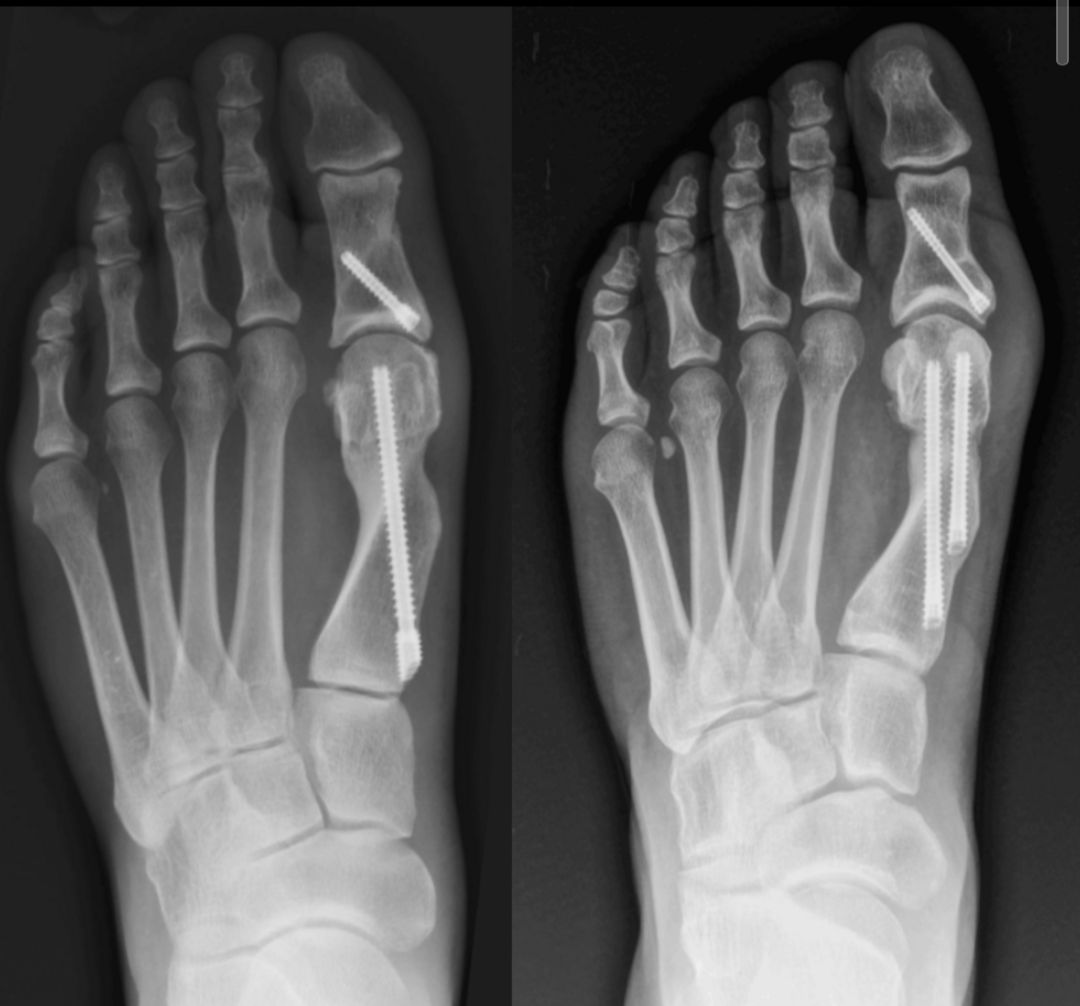

Las fracturas de pierna, pie y tobillo son lesiones frecuentes que pueden producirse por caídas, accidentes deportivos o traumatismos de mayor energía, y requieren una evaluación especializada para evitar secuelas funcionales. Según el tipo de fractura, su localización, el grado de desplazamiento y las características del paciente, el tratamiento varia. Se realiza una evaluación clínica e imagenológica completa para definir la conducta más adecuada en cada caso, que puede incluir manejo conservador con inmovilización o quirurgico de ser el caso. El objetivo es lograr una correcta consolidación ósea, aliviar el dolor y recuperar la función, priorizando una rehabilitación segura y progresiva.

Juanetes

El juanete es una deformidad del dedo gordo del pie que puede generar dolor, inflamación, dificultad para caminar y problemas para usar calzado. Suelen progresar con el tiempo si no se evalúan adecuadamente. Se realiza una evaluación clínica y radiográfica completa para definir el tratamiento más adecuado en cada caso, según la deformidad, los síntomas y la actividad del paciente. El abordaje puede incluir opciones conservadoras o corrección quirúrgica cuando está indicada, con el objetivo de aliviar el dolor y mejorar la función del pie.